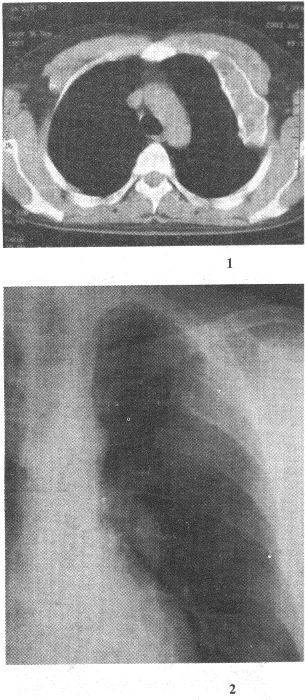

5.男性,40岁。查体发现肋骨病变,X线片和CT片如图。应首先考虑的诊断是![]() |

| 正确答案:D 解题思路:骨纤维异常增殖症病理上正常骨组织被纤维组织或纤维骨样组织取代,骨皮质膨胀,边缘硬化,病变内可有嵴样隆起。 |